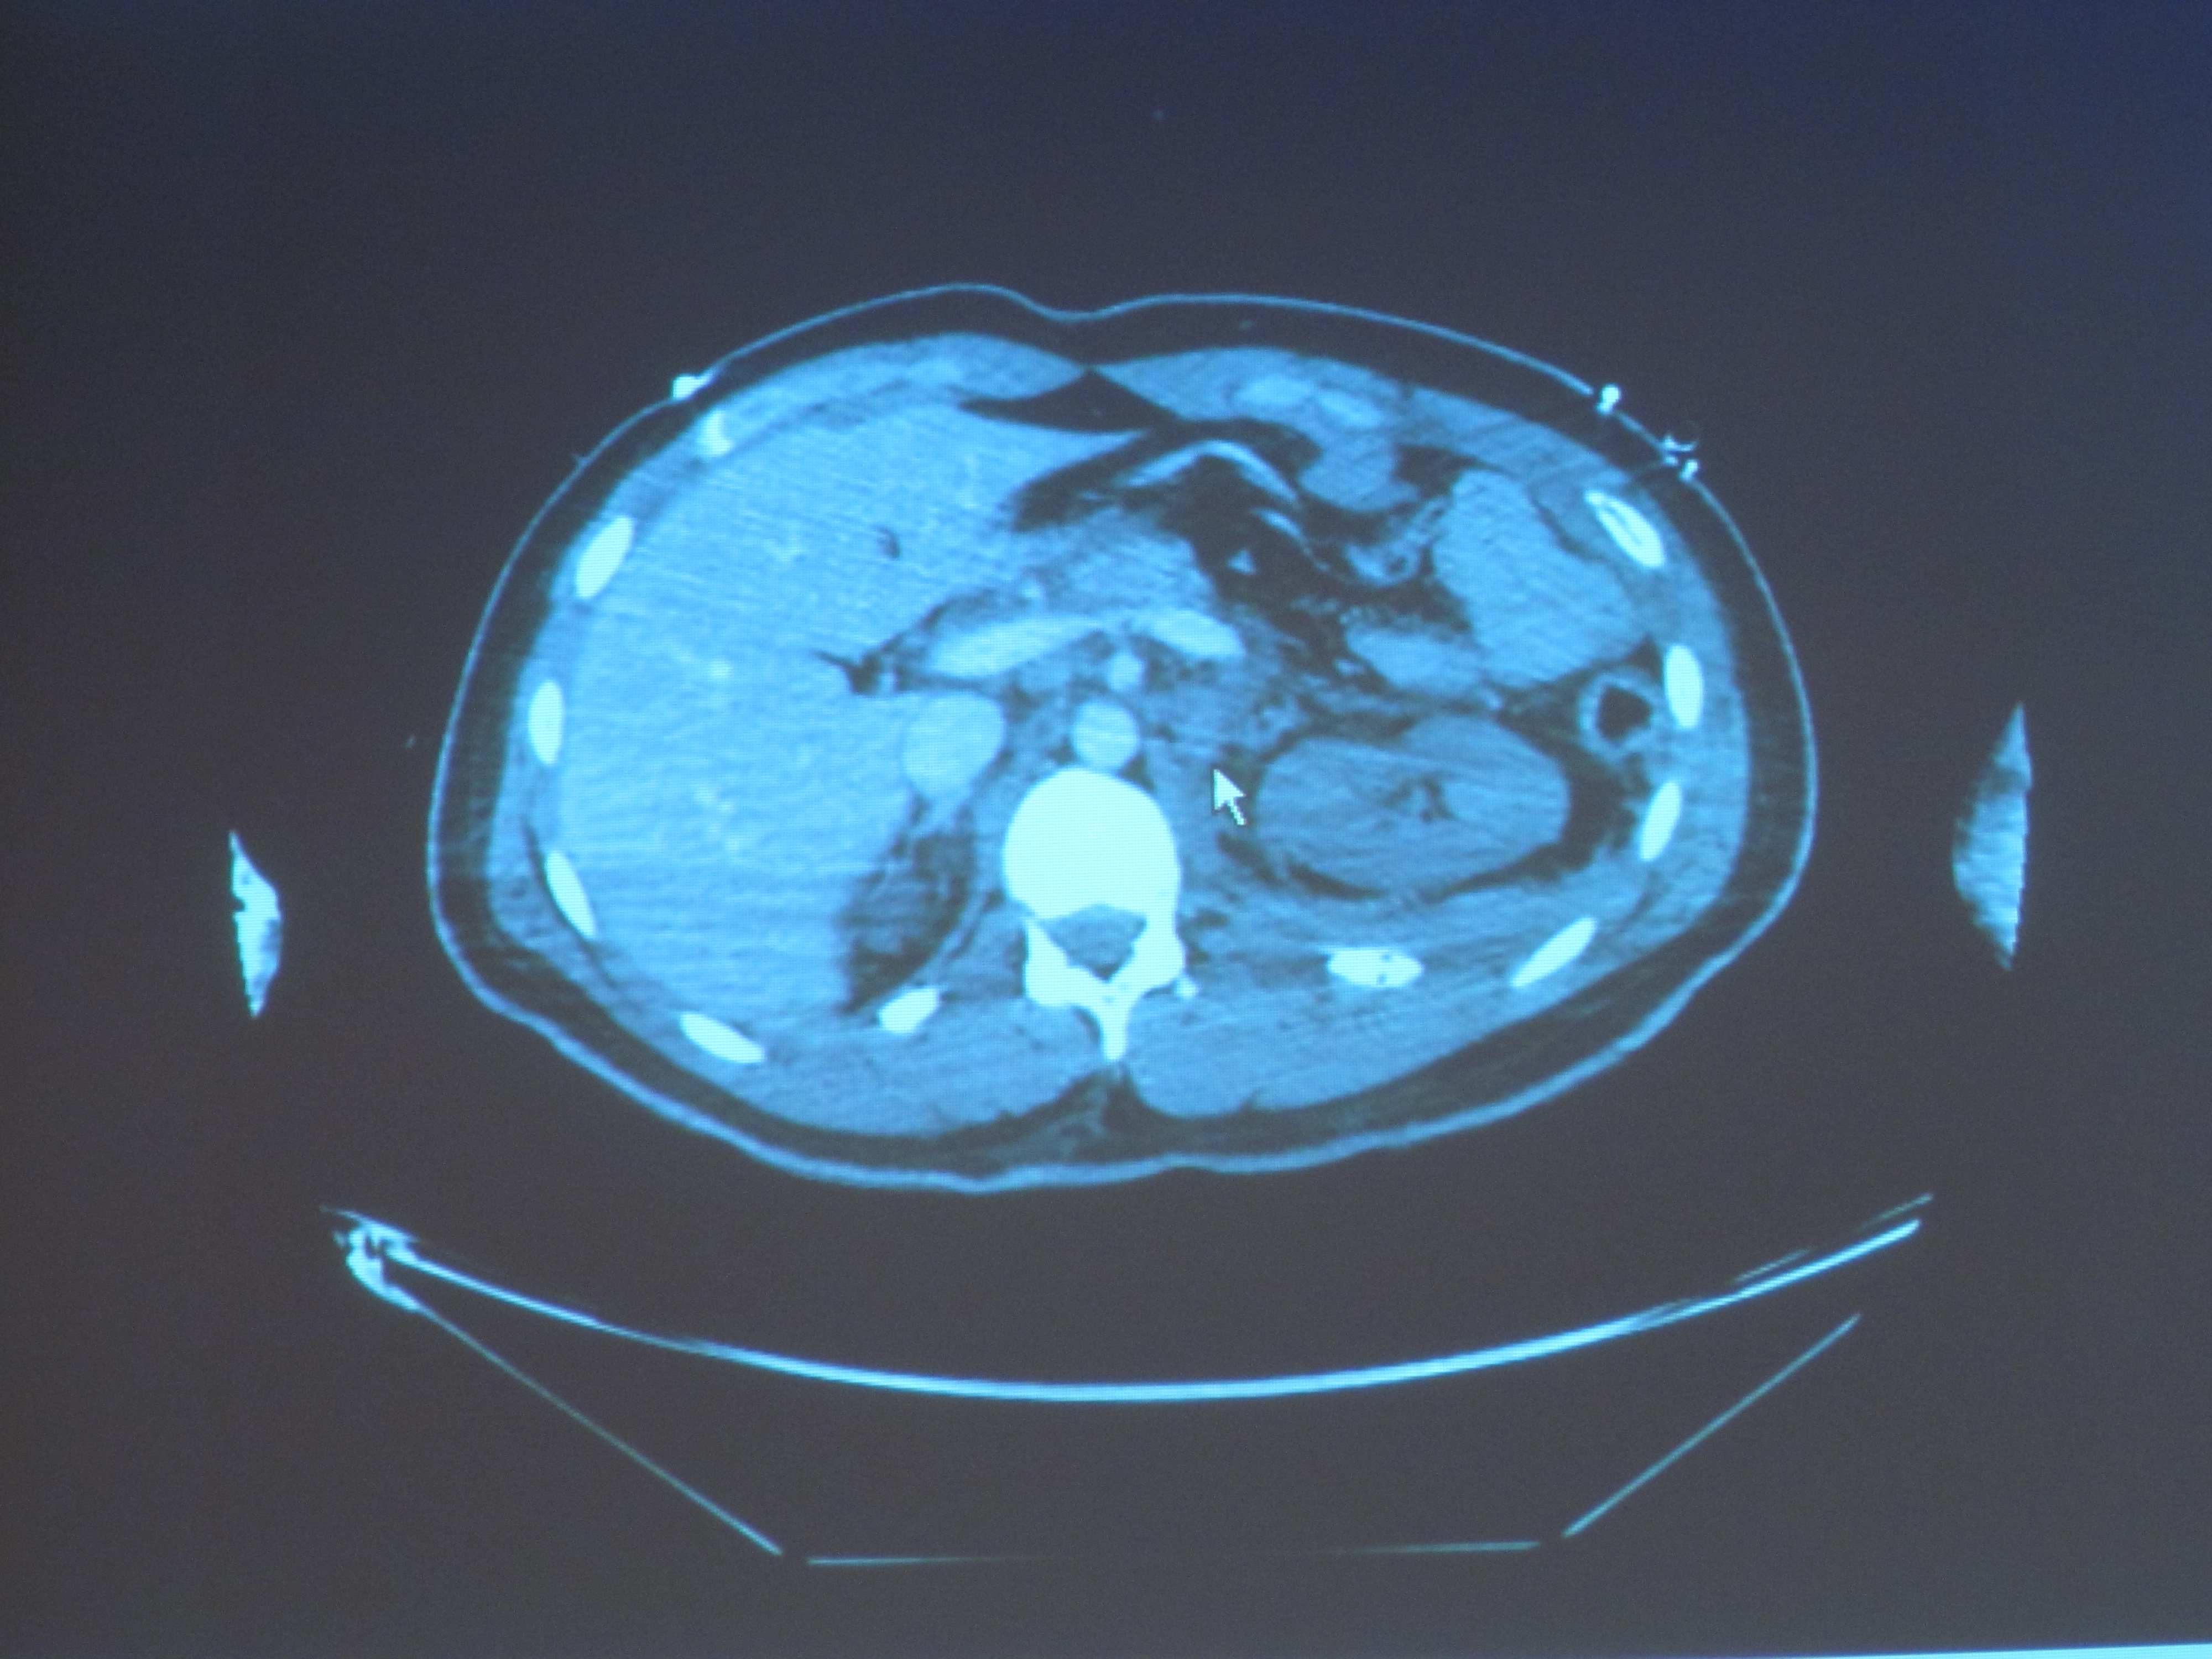

En effet, en radiologie, grâce au  numérique, pour radiographier un corps entier plus de 6 000 plans de  coupe sont réalisés. Le temps où les radiologues travaillaient avec un  seul plan est révolu.

Cliquez sur l'image pour agrandir

Photo  : Scanner d'un patient polytraumatisé (D.R)